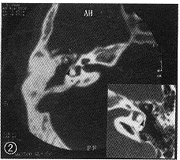

例1 男,21岁, 以反复右耳流脓16年,头晕、呕吐10 d于1998年8月26日入院。查体:右耳道见脓液,耳道深部后上方见3 mm×3 mm×3 mm肉芽,易出血。紧张部大穿孔,瘘管试验(+),Ⅲ度眼震,快相右侧。Weber试验向右。CT示右乳突气化差,鼓室及鼓窦见密度增高影,鼓窦入口扩大,锤骨、砧骨吸收破坏。前庭龛及镫骨底板骨质吸收(图1),半规管骨质破坏,有瘘管形成(图2)。MRI示右上鼓室鼓窦区有密度增高影。脓液培养:表皮葡萄球菌生长。于1998年9月8日行乳突根治术(右),术中见耳道深处充满褐红色质脆肉芽组织,易出血。上鼓室、鼓窦则见褐红色质韧肉芽组织及胆脂瘤,水平半规管见3 mm×1.5 mm椭圆形骨质缺失。锤骨砧骨已吸收破坏,镫骨未见。术后病理报告:右乳突部炎性肉芽组织伴霉菌团形成。术后给大扶康静滴及局部换药。眼震逐渐消失,术后1个月乳突术腔上皮化出院。1年后复查,术腔情况好。

图2 例1右侧颞骨CT横断面扫描:乳突气房浑浊,锤骨及砧骨可见,但周边毛糙。箭头示外半规管骨质吸收破坏,瘘管形成。右下角插图中箭头示对侧正常的外半规管骨质